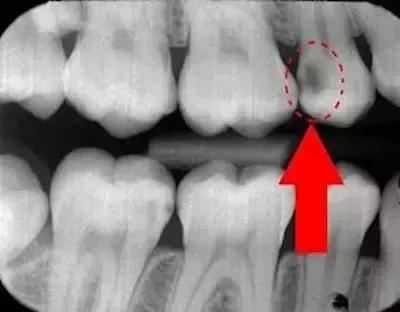

1/ 牙齿的接触面有蛀牙,造成了牙缝变宽。